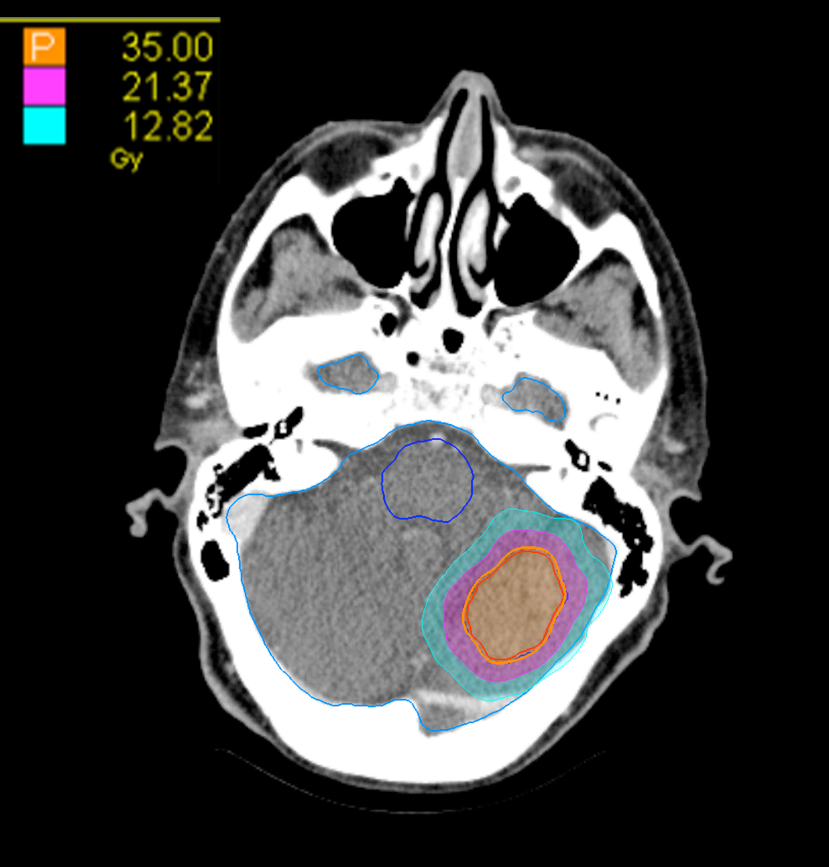

Treatment Plan Images

Dose Distributions

- Prescription to the 82% isodose line

- Max. dose 42.7 Gy

35 Gy in 5 fractions